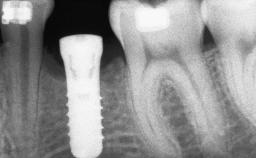

Le Fort I Interpositional Graft and Mandibular Sandwich Osteotomy for Maxillofacial Rehabilitation after Severe Periodontitis

# of Implants 14

Type of Implants Two-Piece

Bone Volume Deficient vertically or deficient vertically AND horizontally